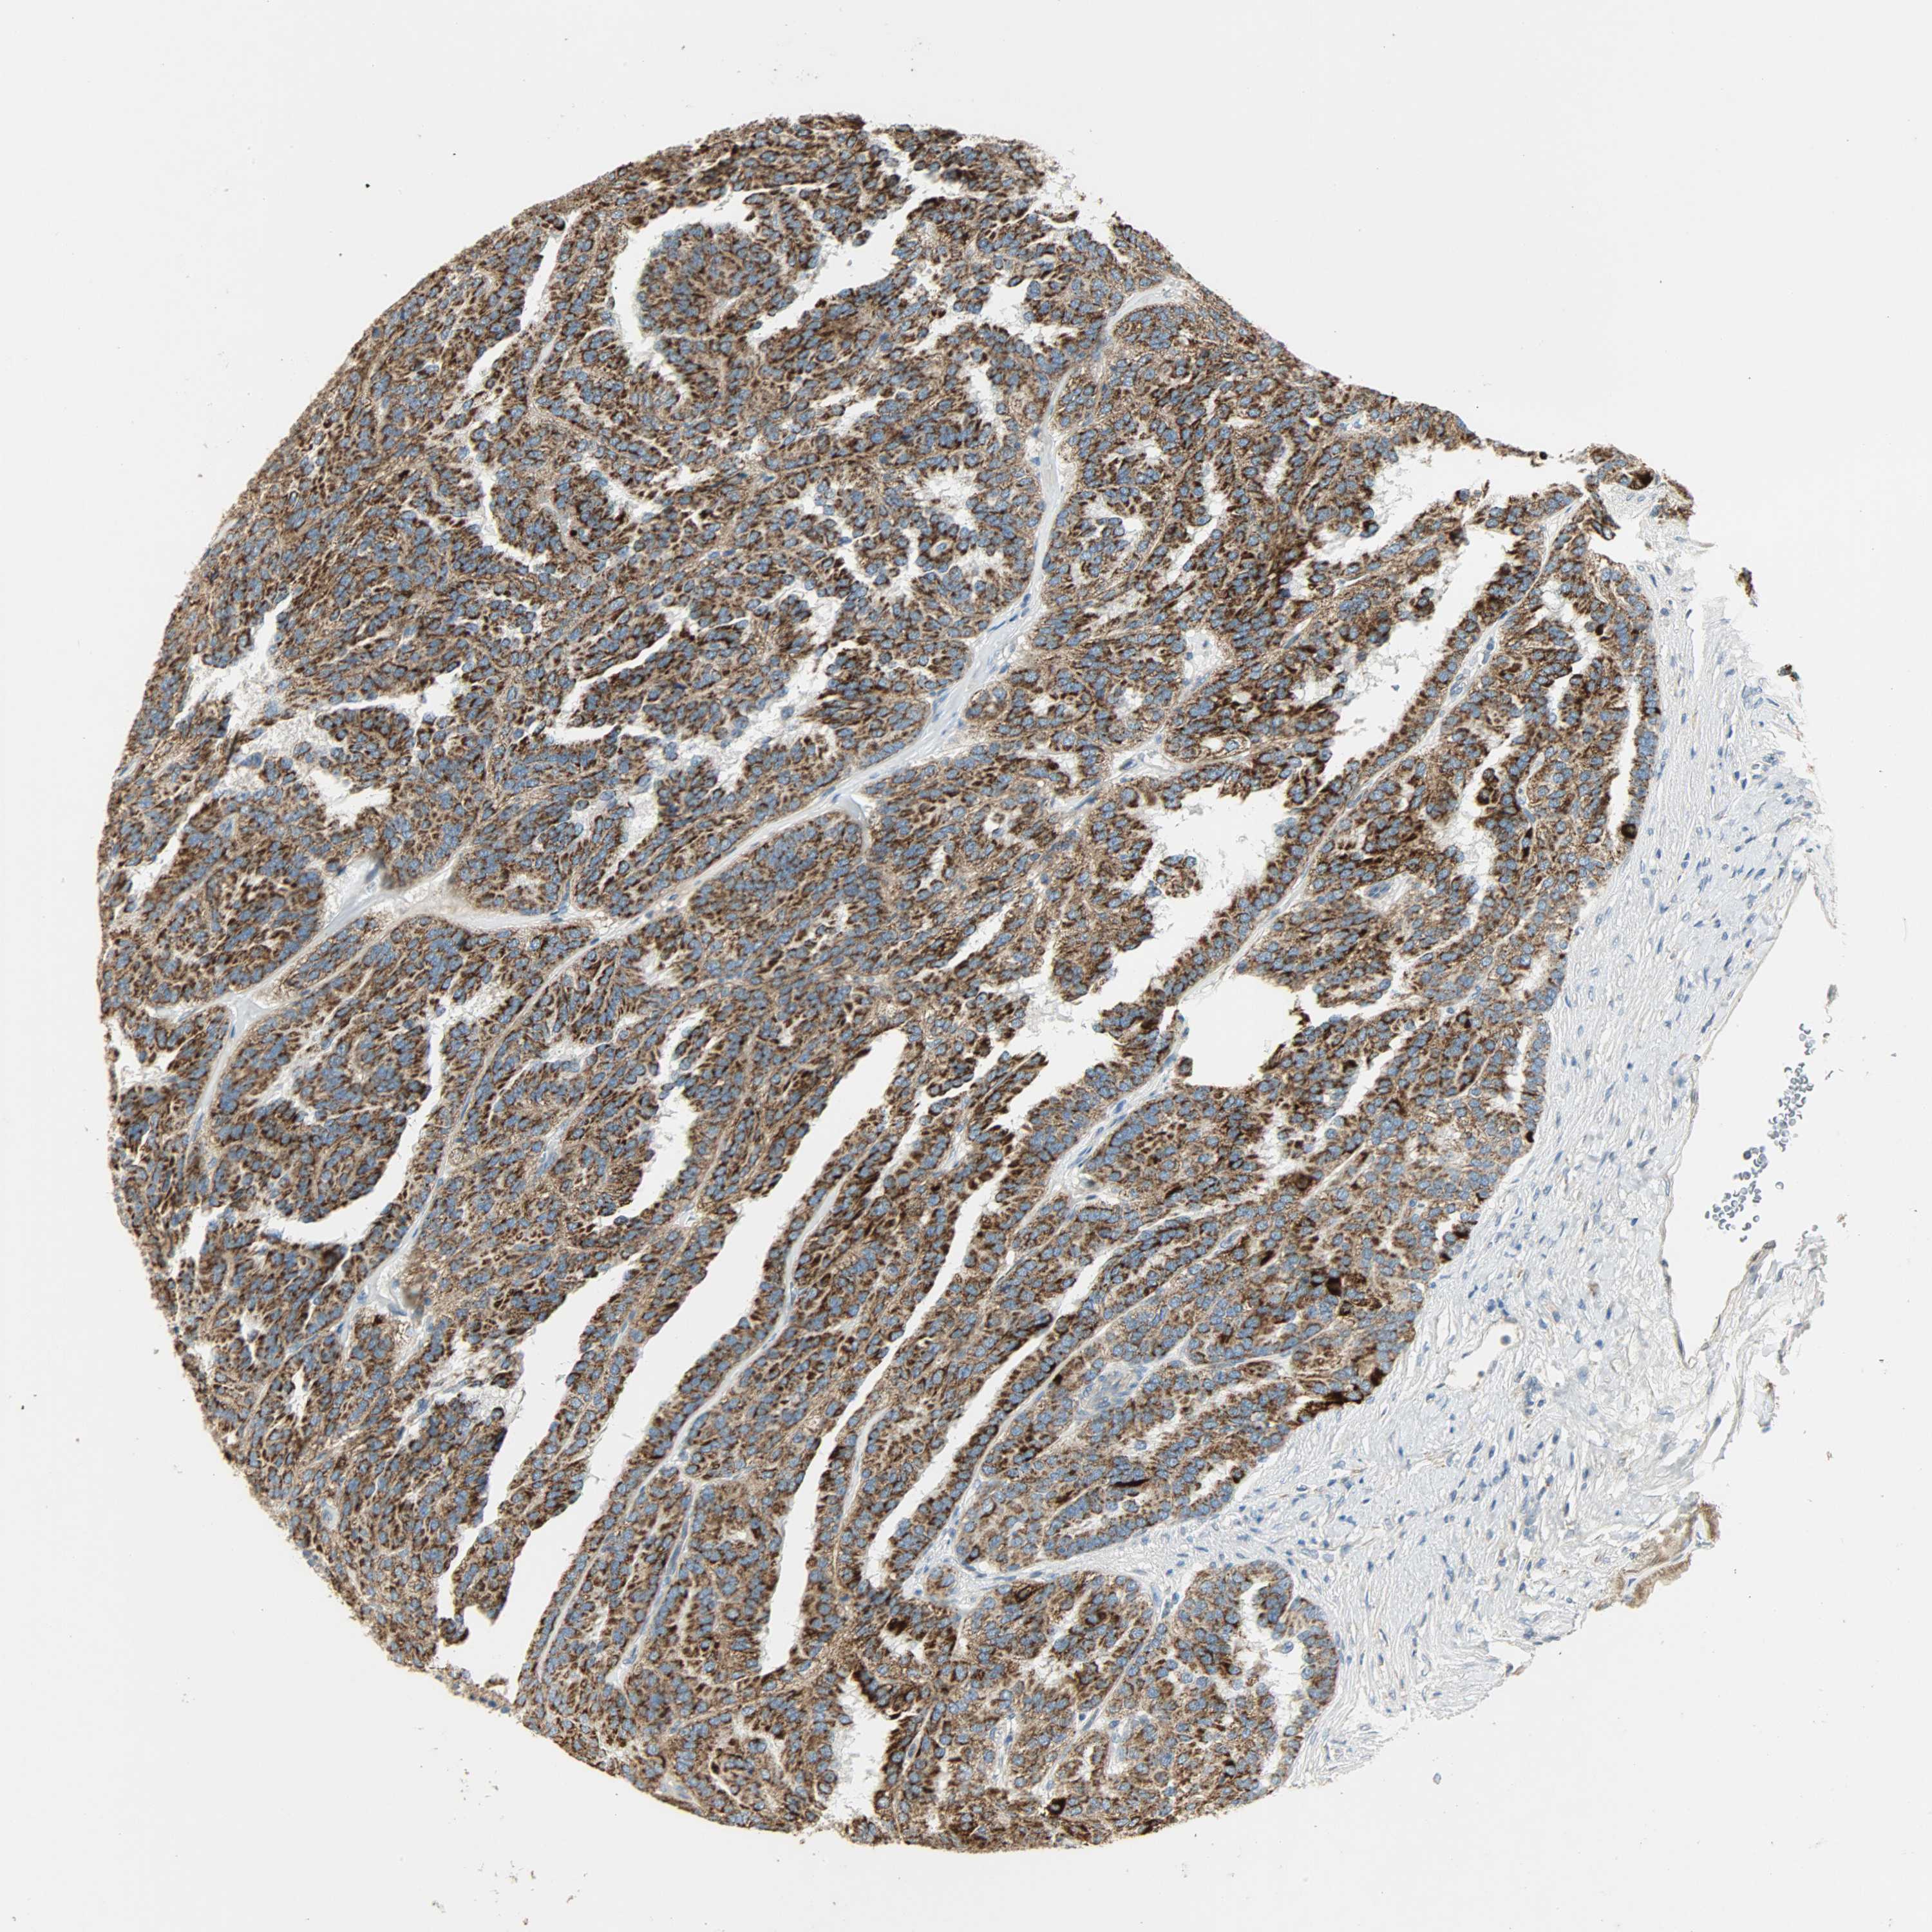

KIDNEY RENAL CLEAR CELL CARCINOMA (TCGA) - Interactive survival scatter ploti

The Survival Scatter plot shows the clinical status (i.e. dead or alive) for all individuals in the patient cohort, based on the same data that underlies the corresponding Kaplan-Meier plots. Patients that are alive at last time for follow-up are shown in blue and patients who have died during the study are shown in red.

The x-axis shows the expression levels (FPKM) of the investigated gene in the tumor tissue at the time of diagnosis. The y-axis shows the follow-up time after diagnosis (years). Both axes are complimented with kernel density curves demonstrating the data density over the axes. The top density plot shows the expression levels (FPKM) distribution among dead (red) and alive patients (blue). The right density plot shows the data density of the survived years of dead patients with high and low expression levels respectively, stratified using the cutoff indicated by the vertical dashed line through the Survival Scatter plot. This cutoff is automatically defined based on the FPKM cutoff that minimizes the p-score. The cutoff can be changed by dragging the vertical line or by entering a cutoff value in the square labeled "Current cut-off".

Under the Survival Scatter plot the p-score landscape (black curve; left axis) is shown together with dead median separation (red curve; right axis). Dead median separation is the difference in median mRNA expression between patients who have died with high and low expression, respectively. It is calculated as follows: median FPKM expression of dead patients with high expression - median FPKM expression of dead patients with low expression. This is intended to aid the user in visually exploring custom cutoffs and the associated p-scores and dead median separation.

Individual patient data is displayed and can be filtered by clicking on one or more of the category buttons on the top of the page. Categories describing expression level and patient information include: high, low, alive, dead, female, male and tumor stages. The scale of the x-axis can be toggled between linear and log-scale by clicking on the "x log" button. Mouse-over function shows TCGA ID, patient information and mRNA expression (FPKM) for each patient.

& Survival analysisi

Kaplan-Meier plots summarize results from analysis of correlation between mRNA expression level and patient survival. Patients were divided based on level of expression into one of the two groups "low" (under cut off) or "high" (over cut off). X-axis shows time for survival (years) and y-axis shows the probability of survival, where 1.0 corresponds to 100 percent.

NNT is potential prognostic, high expression is favorable in Kidney Renal Clear Cell Carcinoma (TCGA)

Best expression cut offi

Based on the FPKM value of each gene, patients were classified into two groups and association between prognosis (survival) and gene expression (FPKM) was examined. The best expression cut-off refers the FPKM value that yields maximal difference with regard to survival between the two groups at the lowest log-rank P-value. Best expression cut-off was selected based on survival analysis .

When clicking on this number, the vertical dashed line indicating cut-off, the interactive survival plot, and the Kaplan-Meier curve will be adjusted to show results based on the best expression cut-off.

: 13.37

TCGA RNA samplesi

RNA-seq data is reported as average FPKM (number Fragments Per Kilobase of exon per Million reads), generated by the The Cancer Genome Atlas (TCGA) .

Normal distribution across the dataset is visualized with box plots, shown as median and 25th and 75th percentiles. Points are displayed as outliers if they are above or below 1.5 times the interquartile range. FPKM values of the individual samples are presented next to the box plot.

Average pTPM 21.8

Number of samples 521